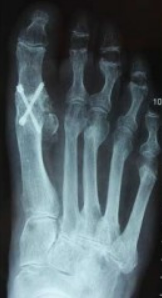

Chirurgie

Le but est de soudé l'articulationn usé (arthrodèse) à l'aide de vis ou d'une plaque